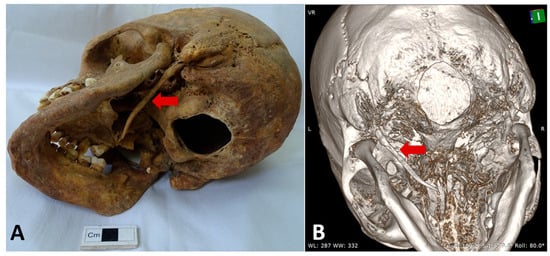

| Anatomical landmarks | MPR reconstruction using the orbito-meatal sagittal plane, with oblique adjustment in the axial plane. Length: 33 mm measured in the coronal plane. |

| Reference planes | Dimensional assessment from the inferior surface of the petrous part of the temporal bone |

| 3D Model | 3D reconstruction—length: 31.2 mm |